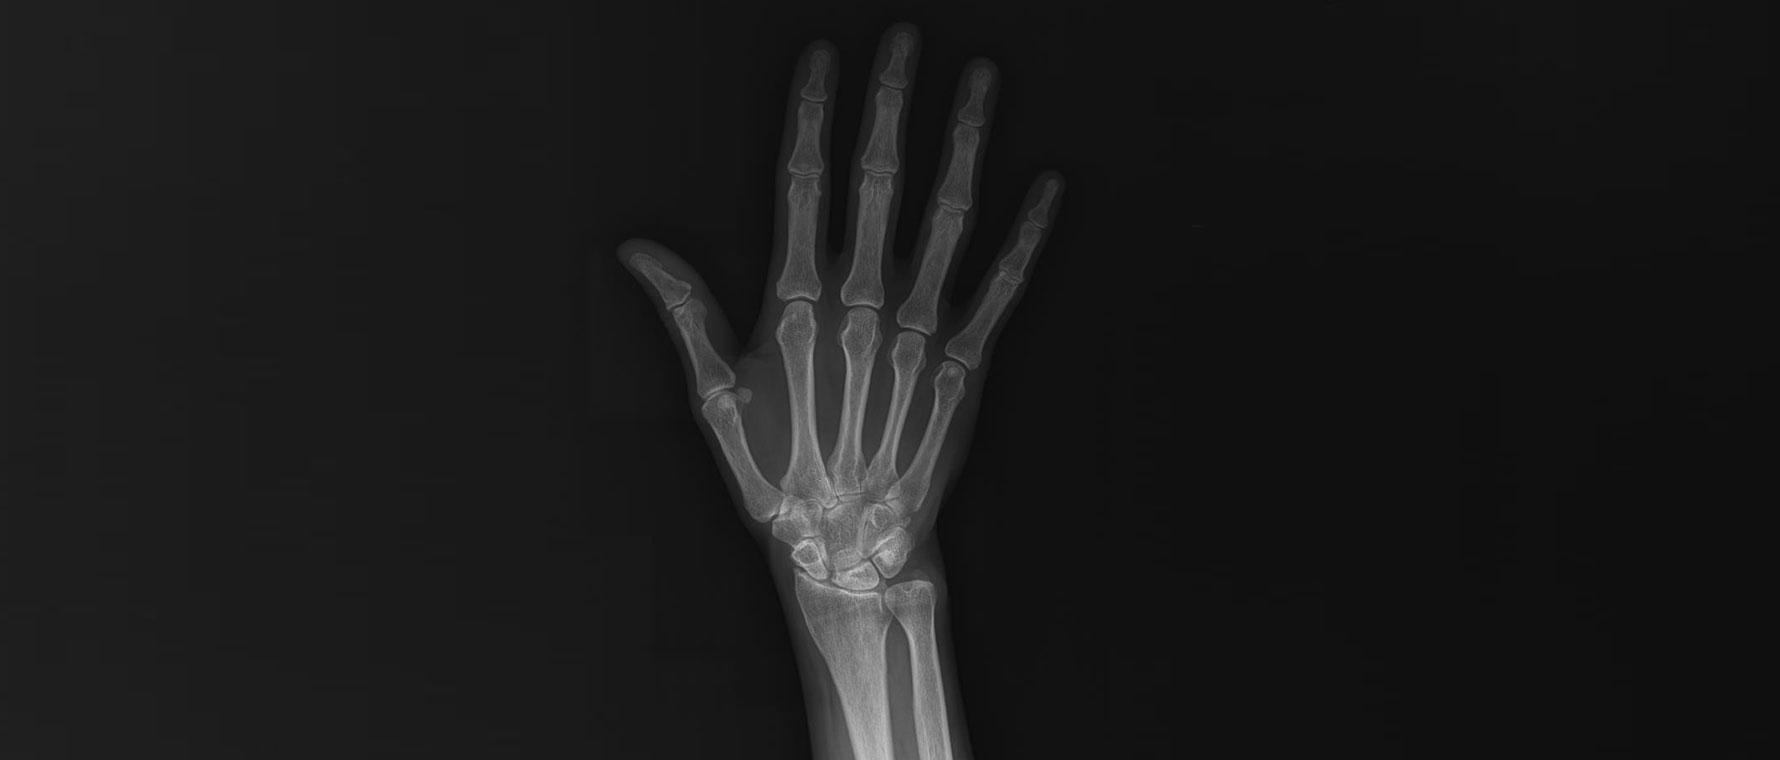

El Bileği Kireçlenmesi

El bileği kireçlenmesi, eklem kıkırdağının aşınması sonucu ağrı ve hareket kısıtlılığıyla seyreden bir hastalıktır. Travmalar, bağ yaralanmaları ve eski kırıklar en sık nedenlerdir. Hastalar bilekte sertlik, şişlik ve güç kaybı tarif eder. Tanı muayene ve görüntüleme ile konur. Tedavide ağrı kesiciler, atel ve fizik tedavi uygulanabilir. El bileği kireçlenmesi ağırlaşmamış hastalarda kısmi olarak el bileği dondurularak hem ağrı hafifletilir hem de el bileği hareketleri kısmi olarak korunur. Buna karşın ilerlemiş hastalarda tüm el bileğinin dondurulması ameliyatı yapılır.